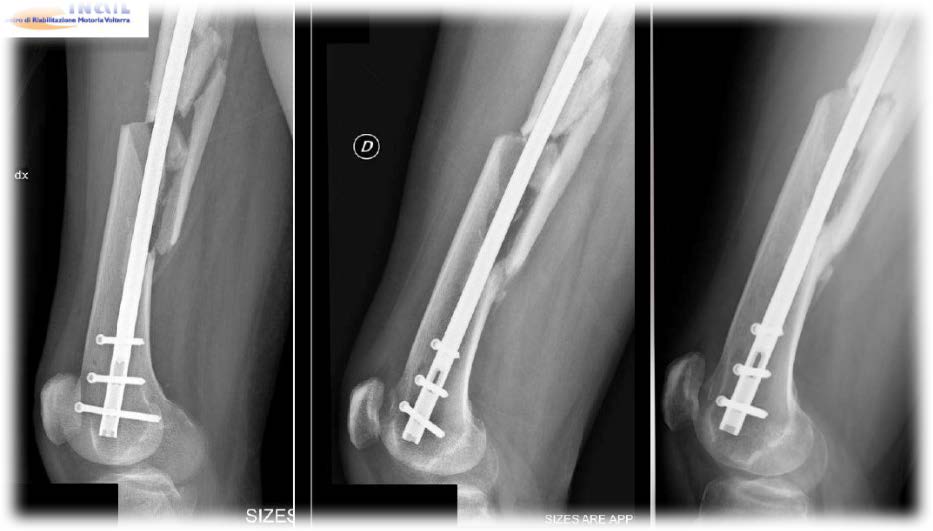

Funguje velmi dobře bezprostředně po operacích a je možné ji použít s protézami, plátky a syntetickými médii jakéhokoliv druhu.

Kompatibilní s implantáty a chirurgickými plotýnkami

Možnost aplikace ihned po úrazu nebo chirurgickém zákroku

Co se týče kostí, LIMFA Therapy je schopna zkrátit čas hojení o 50 %.